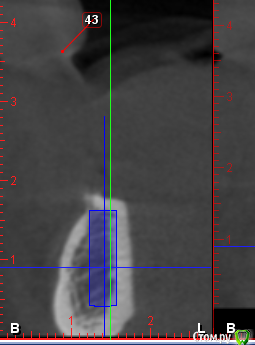

Sergiosse Опубликовано 7 декабря, 2015 Поделиться Опубликовано 7 декабря, 2015 (изменено) Пациентка 67 лет с полной адентией. Установил 2 импланта в обл 33,34 зубов. Заглубил относительно язычной стенки на 1 мм, по гребню 2мм. Вестибулярно осталась-голая резьба 2- 2.5мм . Хотел набрать аутокость со сверла,ее не оказалось. Ушил.Переживаю. Плантруется установка полного сьемного протеза с фиксацией болл аттачменами.Что посоветуете ? PS Имплант встал не как на скриншоте, а левееи выше. Изменено 7 декабря, 2015 пользователем Sergiosse Ссылка на комментарий